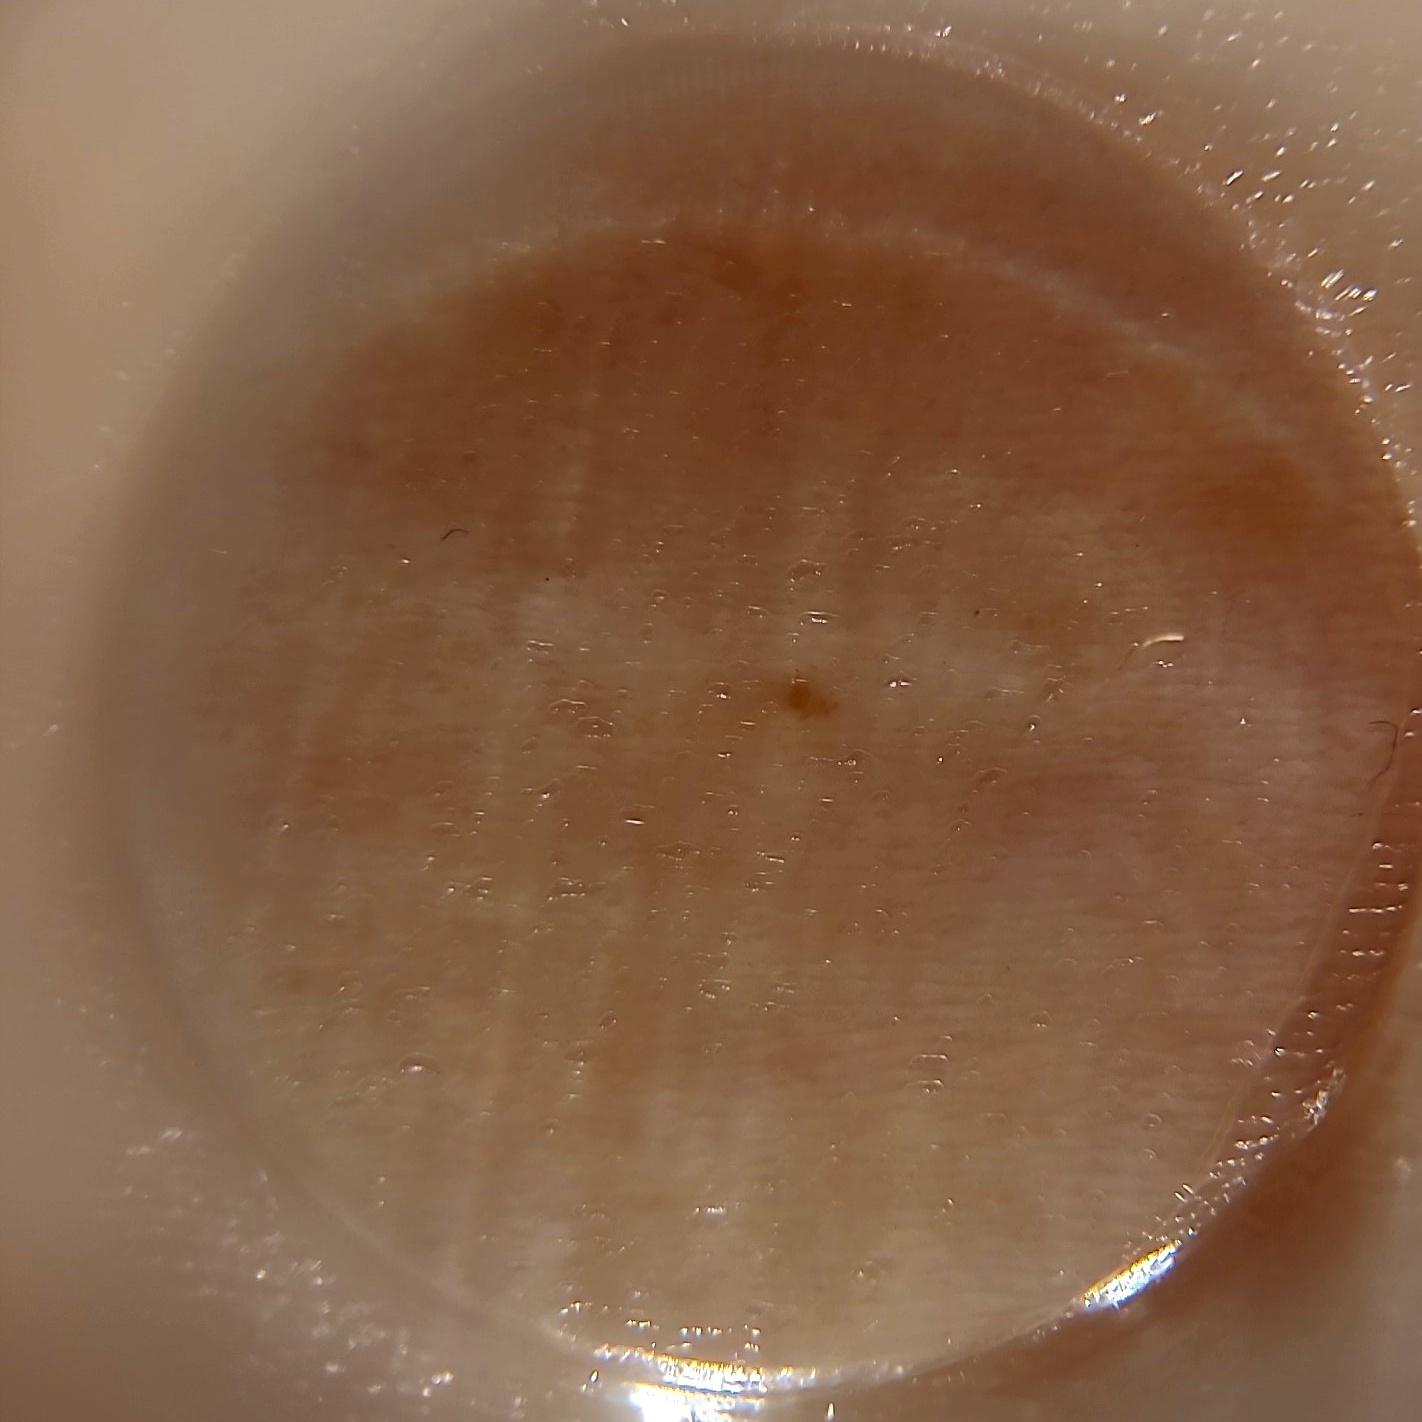

ISIC_1803958

1422 x 1422

Clinical

Field Value

acquisition_day 112

age_approx 45

anatom_site_1 Upper extremity

anatom_site_general upper extremity

diagnosis_1 Benign

diagnosis_confirm_type single image expert consensus

image_type dermoscopic